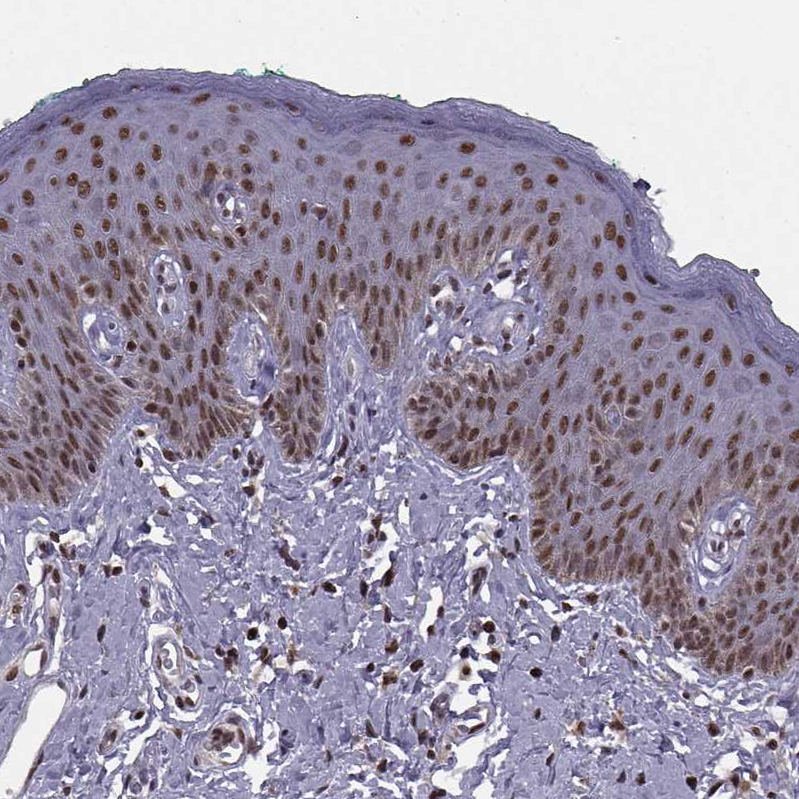

Immunohistochemical staining of human fallopian tube shows strong nuclear positivity in glandular cells.